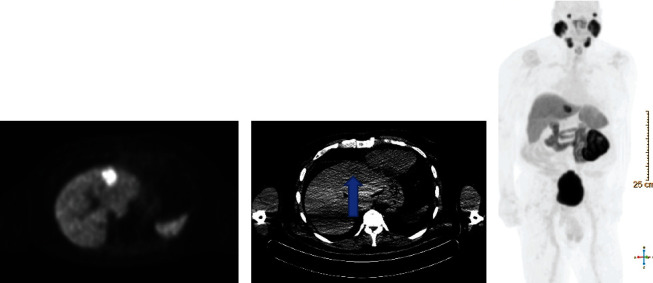

Prostate-specific membrane antigen positron emission tomography (PSMA PET) has been approved by the Food and Drug Administration (FDA) to identify prostate cancer in the setting of biochemical recurrence but can also identify other malignancies. 18F-PSMA PET has not been studied as a potential tool for hepatocellular carcinoma (HCC). We describe the case of a 76-year-old male with a rising prostate-specific antigen (PSA) after definitive prostate cancer treatment and no prior liver pathology who was incidentally found to have HCC on 18F-PSMA PET.

Abstract Image